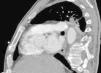

Varón de 63 años, esplenectomizado y sin vacuna antineumocócica. Ingresa con neumonía izquierda y derrame paraneumónico (empiema). Durante colocación de tubo de drenaje pleural (TDP) se aprecia sangrado profuso, pinzándose el mismo. En TAC de tórax (figs. 1 y 2) se objetiva TDP en pared posterior de arteria pulmonar izquierda sin sangrado activo. Mediante toracotomía se observa TDP que perfora parénquima pulmonar hasta introducirse en pared posterior de arteria pulmonar, identificándose sangrado arterial tras la movilización cuidadosa del TDP. Se consigue hemostasia tras realización de bolsa de tabaco que engloba la entrada arterial del TDP. El postoperatorio transcurrió sin complicaciones.